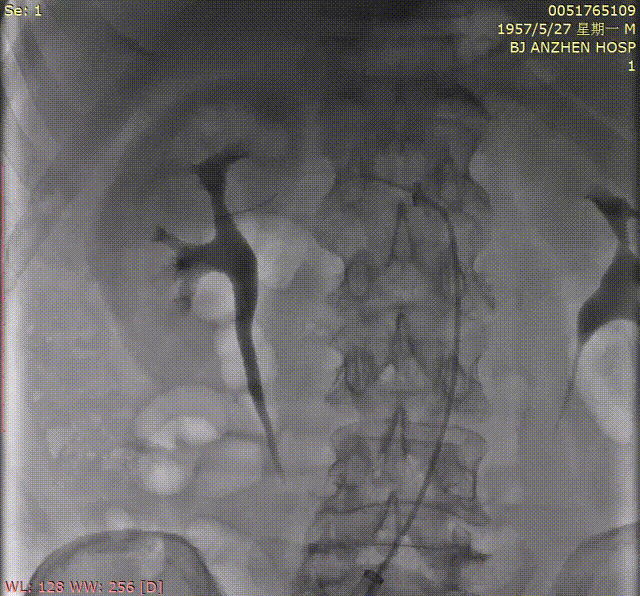

1.根据术前测量分析,采取右侧股动脉作为主入路,左股为辅入路。置入猪尾进行根部造影,造影可见主动脉根部少量钙化,少量反流。

根部造影

7.TAVR术后,行肾动脉造影,造影提示右侧肾动脉近端局限性狭窄,程度约80%。

肾动脉造影